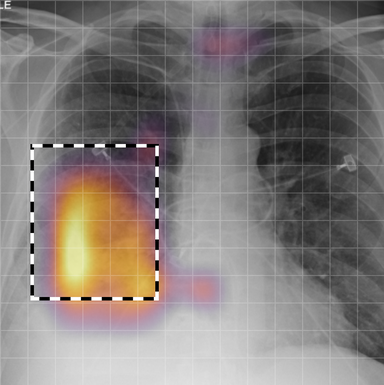

| (1) |

for , where denotes 2D sinusoidal positional encodings [12] and is its temporal counterpart, which is learnt (Fig. 2) [4]. The layer-normalised () [6] output of the final transformer encoder block is an ‘aggregated’ representation of patch-level progression information anchored on the current image. Figure 3 shows attention roll-out [1] applied to after pre-training, showing how the prior image contributes to the fused representation. Figure A.5 further highlights the robustness to variations in pose underlining that registration is not necessary for this encoder.

In Figure A.3, we show examples of self-attention rollout [1] maps for pleural effusion and consolidation, including radiologist-annotated bounding boxes surrounding the corresponding pathology in each prior and current image.

To model the attention flow through the transformer encoder block, we first average each attention weight matrix across all heads, subsequently we multiply the matrices between every two layers. For every block we add the identity matrix in order to model the residual connections. Last, we only keep the top 10 of attention weights per block to reduce noise in the final rollout map. In contrast to [21], we do not visualize the rollout map with respect to a [CLS] token. Instead, we choose a reference image patch from the center of the radiologist-annotated bounding boxes, marked with in Figure A.3.

We find that the rollout maps in Figure A.3 are in good agreement with radiologist-annotated bounding boxes, i.e., the reference patch attends to other patches within the bounding boxes in the prior and current image. In addition, we find that BioViL-T is robust to pose variations, e.g., in Figure A.3 (a) we show that despite the vertical shift between prior and current image, the reference patch attends to the correct image patches in the prior image.